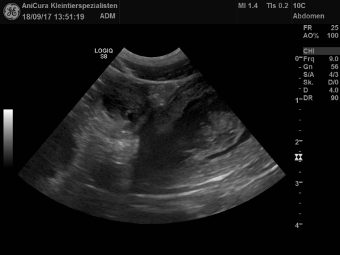

| 18.09.2017 |

| Uaine ist schwanger. Die Ultraschallbilder beweisen es. |